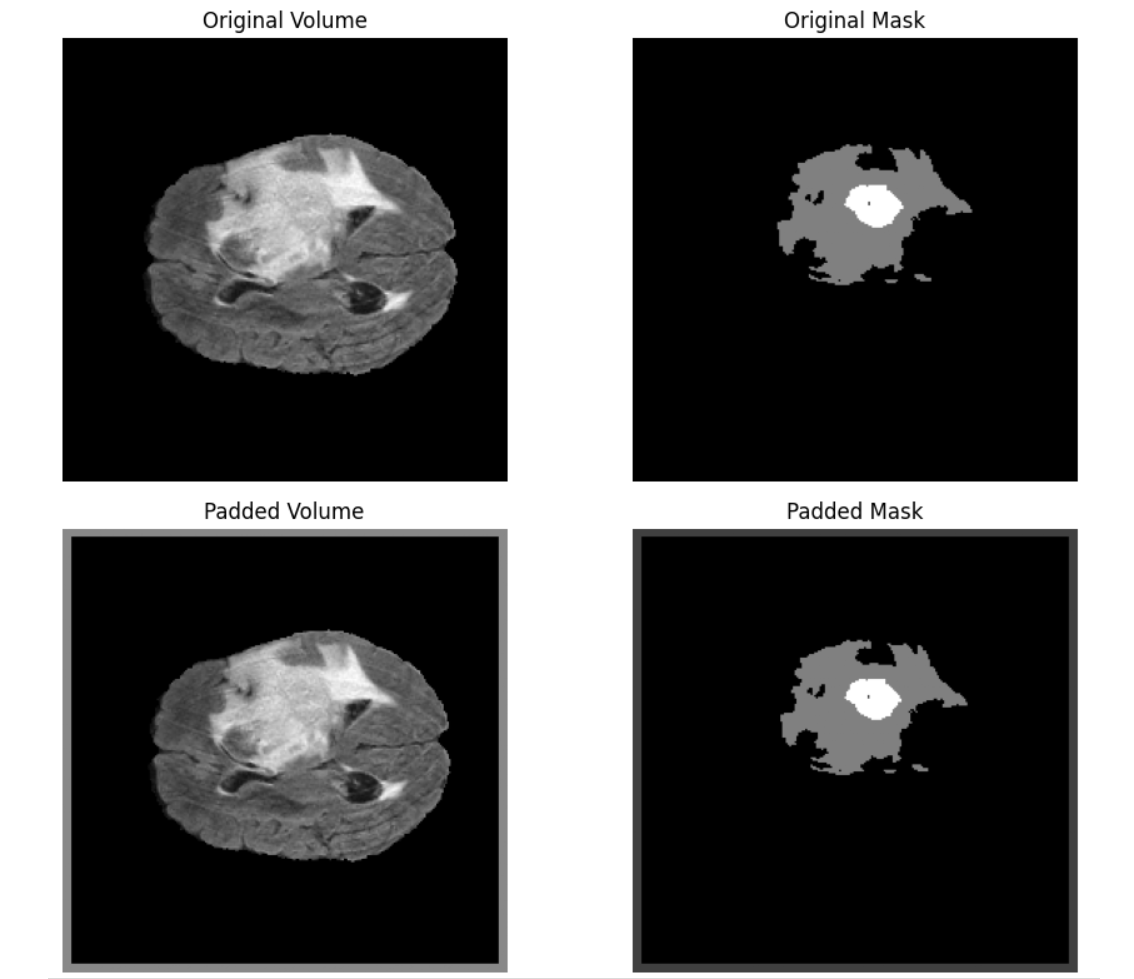

Pad3D: Add padding to 3D volumes, like medical scans, along the depth, height, and width dimensions. Padding adds extra voxels (3D pixels) on the sides of a volume and is often used to ensure a consistent shape across all samples or to prevent cropping of features during convolution.

Key parameters used are:

padding: Specifies how much to pad each dimension.intpads all 6 sides (front/back, top/bottom, left/right) equally.tuple[int, int, int]pads symmetrically on all sides of each dimension (e.g. depth, height, width).tuple[int, int, int, int, int, int]allows different padding values for each side explicitly e.g. (depth_front, depth_back, height_top, height_bottom, width_left, width_right)fill(float or tuple): The value used to fill the padded voxels in the image volume. Default is 0.fill_mask(float or tuple): Fill value used for the mask (if provided). Default is0.p(float): Probability of applying the padding. Default is1.0(always apply).

# Load 3D volume and mask

volume = nib.load("/content/BraTS20_Training_001_flair.nii").get_fdata().astype(np.float32)

mask = nib.load("/content/BraTS20_Training_001_seg.nii").get_fdata().astype(np.uint8)

# Apply Pad3D transformation

transform = A.Pad3D(

padding=(5, 5, 5), # Pad depth, height, width by 5 on each side

fill=225,

fill_mask=1,

p=1.0

)

augmented = transform(volume=volume, mask3d=mask)

vol_aug = augmented["volume"]

mask_aug = augmented["mask3d"]

Following is the output.